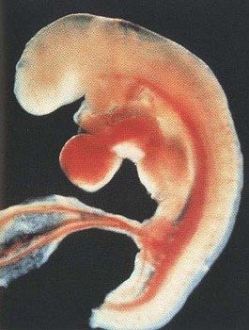

3 SG / 5 SA

La 3ème semaine de grossesse correspond à 5 SA (semaines d’aménorrhée). Sautes d’humeur, seins douloureux, nausées matinales… les changements annoncés commencent peut-être à pointer le bout de leur nez. Explications.

Côté bébé

L’œuf s’est allongé mais reste minuscule. Votre bébé mesure en effet moins de 2 millimètres.

Son développement à 3 semaines de grossesse :

Le fœtus ressemble à une petite crevette de la taille d’un grain de riz. Néanmoins, on distingue déjà une tête et une queue. Sur l’arrière, on voit une ligne, première ébauche du tube neural qui deviendra le cerveau et la moelle épinière. Le placenta et le cordon ombilical poursuivent eux aussi leur croissance, même s’ils sont encore loin d’atteindre leur pleine maturité.